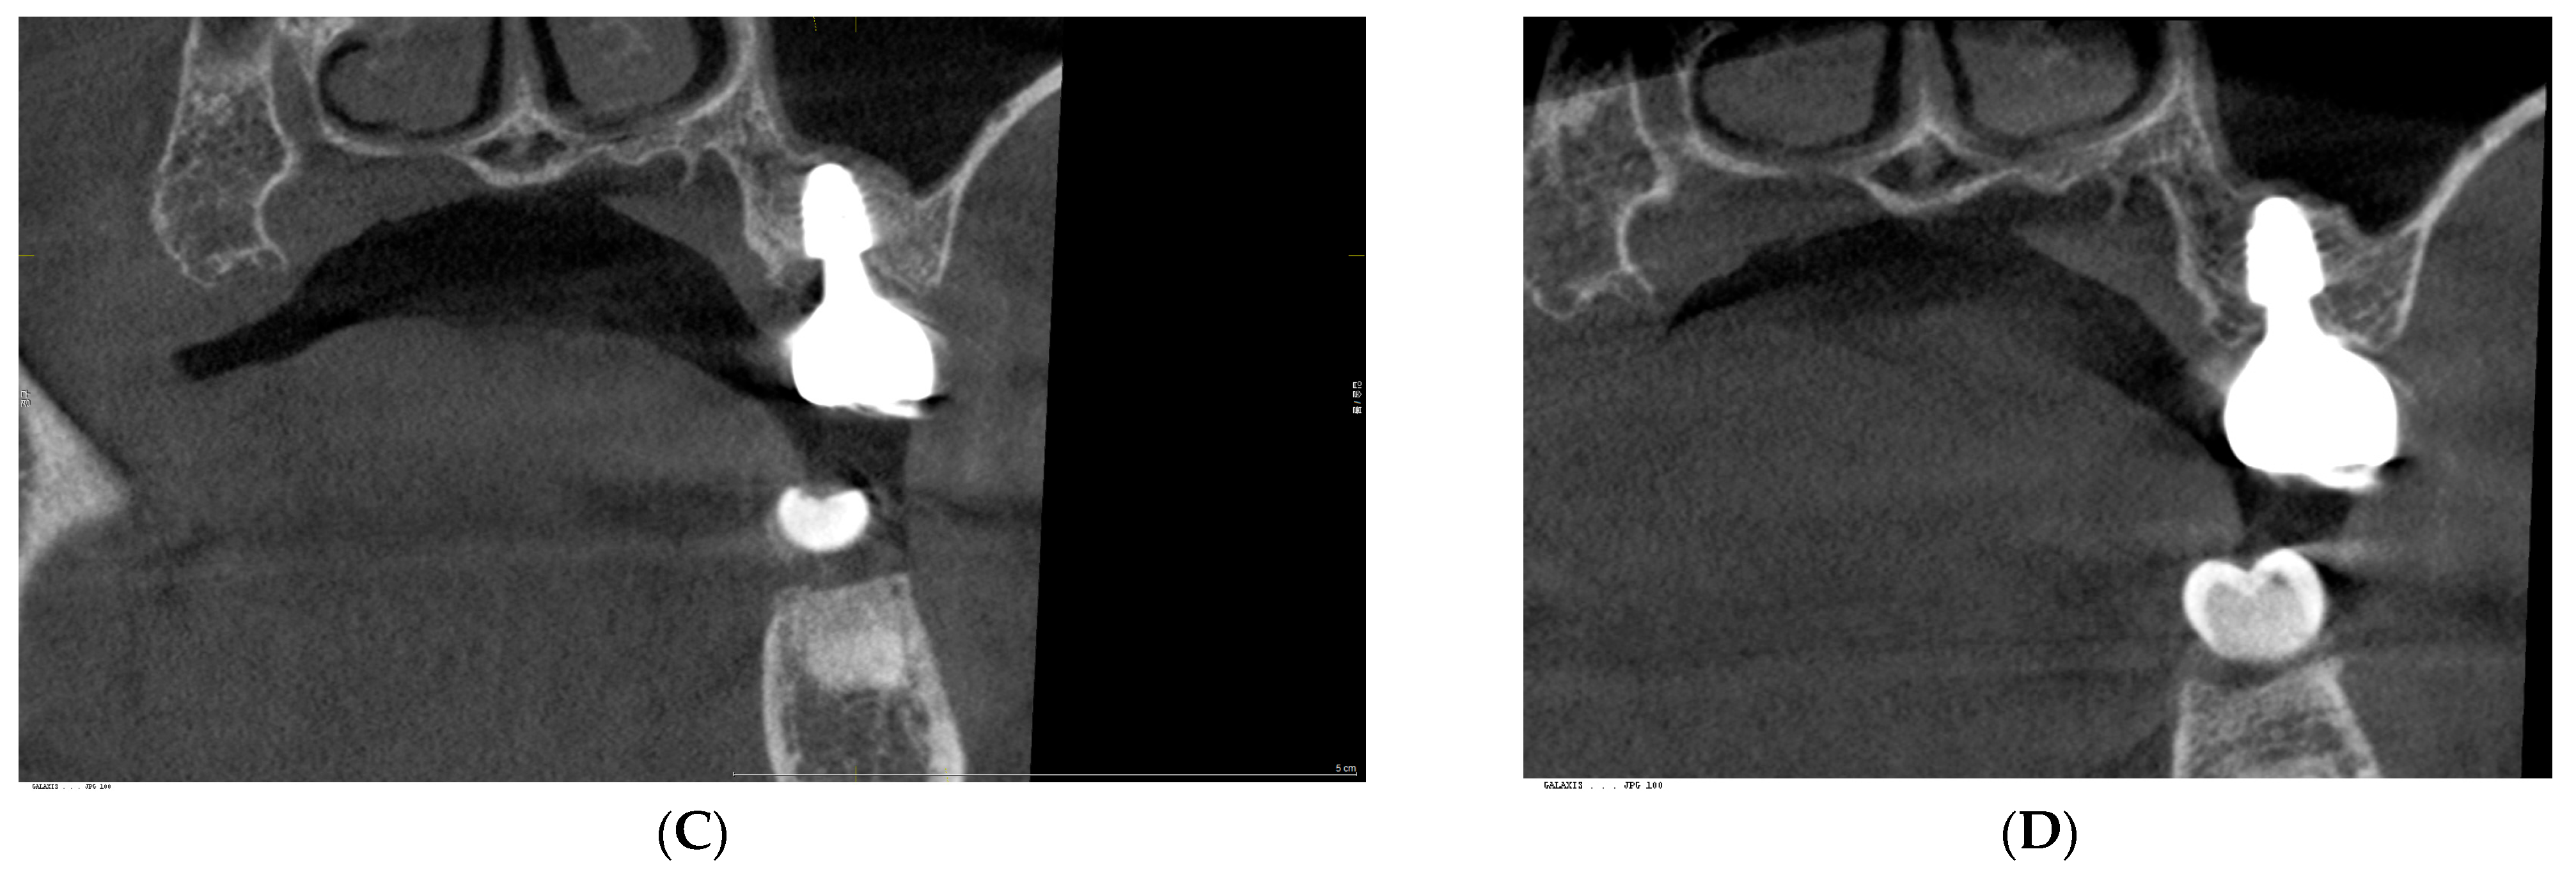

2. Case Presentation

3. Radiographic and Clinical Findings